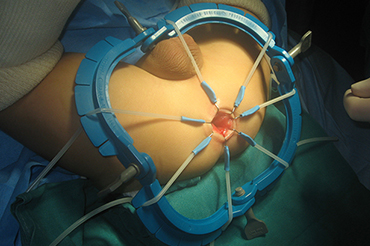

Enfermedad de Hirschsprung